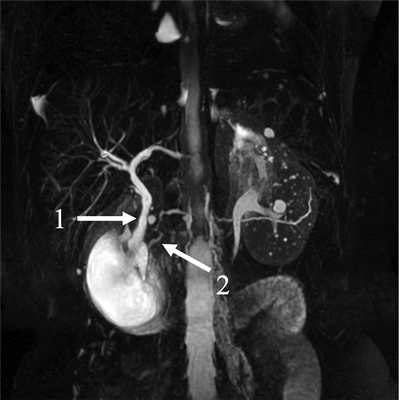

Исследование дополнено магнитно-резонансной холангиопанкреатографией (МРХПГ), по данным которой общий желчный и панкреатический протоки впадают в кистозную структуру с тонкими стенками, расположенную по медиальной стенке ДПК и деформирующую ее просвет (рис. 2).

Рис. 2. МРХП-грамма. Дупликационная киста двенадцатиперстной кишки.

Общий желчный проток (1) и проток поджелудочной железы (2). Панкреатическая и билиарная гипертензия отсутствуют.